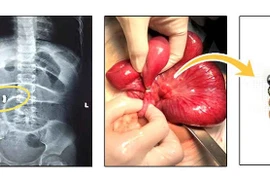

Phẫu thuật thành công ca u nang lách khổng lồ cho bệnh nhi ở Nghệ An

Sau phẫu thuật, bệnh nhi hồi phục nhanh, không ghi nhận biến chứng, có thể ăn uống và vận động nhẹ.